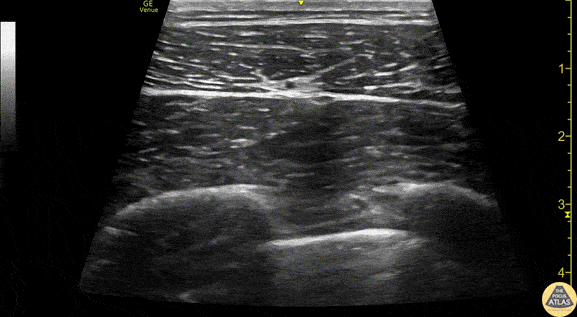

Anatomy of the serratus anterior, as obtained using a linear transducer in a transverse orientation at the level of the 4th/5th rib in the mid axillary line. Anterior is at the left of the image. The latissimus dorsi muscle is seen most superficially, with the serratus anterior muscle deep to it, just above the hyperechoic ribs. Sliding pleura can be seen below the ribs. The thoracodorsal artery can be seen pulsating in the fascial plane between latissimus dorsi and serratus anterior. Drs. Sam Paskin-Flerlage, PGY4 and Michael Heffler, PGY3 Denver Health Residency in Emergency Medicine